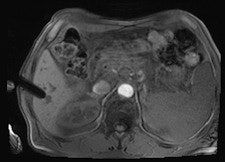

All procedures were performed using a wide-bore 1.5-tesla MR system (Magnetom Espree, Siemens Healthcare). A radiofrequency-shielded liquid-crystal display monitor was installed next to the magnet for real-time monitoring. During the procedures, imaging was performed with the use of a flexible four-channel body-array surface coil and a loop coil, and biopsies were performed with MR-compatible puncture needles. To obtain the specimen, an MR-compatible biopsy device (MRI Biopsy Handy, Somatex Medical Technologies) was used in 36 cases. After placing the MRI-compatible puncture needle in the magnet, two intramuscular biopsies were performed using a non-MR-compatible spring-loaded biopsy gun (ASAP, Boston Scientific) outside the magnet. During the biopsy, vital parameters were monitored using an MR-compatible patient monitor (Invivo 4500 MRI, Invivo Research).

In nine cases -- eight soft-tissue, one liver -- MR fluoroscopy was used to define the entry site, and the physician used a fingertip or water-filled syringe as a marker. In 29 cases -- 11 soft-tissue, 18 liver -- a marker capsule (Adalat, Bayer) was affixed to the supposed entry side with adhesive tape, and the position was corrected after application of conventional sequences. After sterile draping, administration of local anesthesia and skin incision, an MR-compatible puncture needle (14-18 G) was placed subcutaneously outside the magnet.